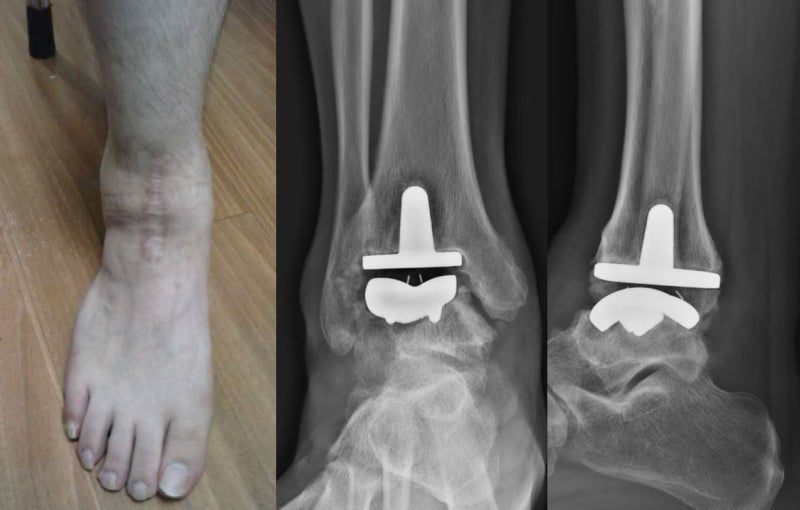

발목 인공관절 수술 후

발목 인공 관절 수술을 할 때 가장 중요한 것은 운동입니다.이는 재발 방지 및 복구 단계를 통해 재발 방지 및 복구 단계를 통해 신속하게 복구 단계를 신속하게 복구할 수 있습니다.발목 인공 관절 수술은 많지만 무릎 관절과 힙합 관절과 힙합 관절에 비해 높은 고장률이 높기 때문에 주의해야 한다.또한 인공 관절 수술 실패 후 다양한 발 관절질환 치료 실패 이후 치료의 지식은 중요하다.#아 인공 관절 수술